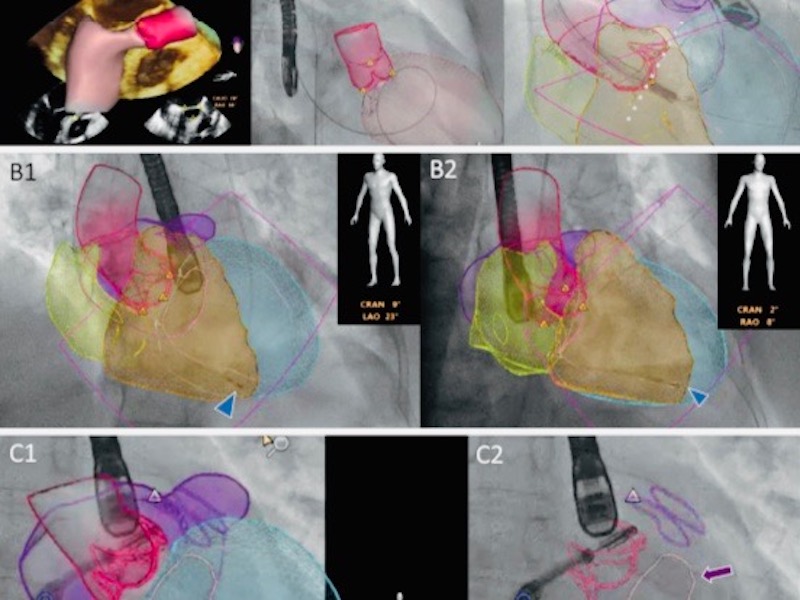

3D model with fluoroscopy (heart imaging)

Potential of fusion imaging and automated three-dimensional cardiac segmentation [...]

Automated anatomical intelligence: next-generation fusion imaging for structural heart [...]